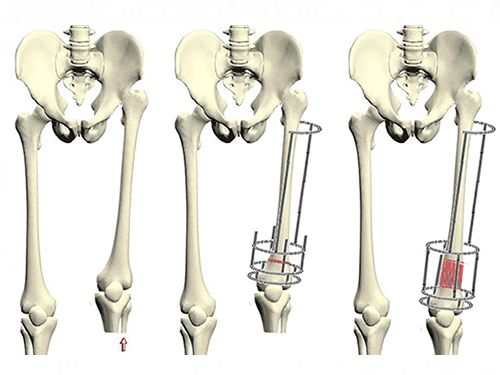

Хирургическое лечение ахондроплазии оправдано только в случаях значительных деформаций конечностей или сужения спинномозгового канала. В таких ситуациях может быть проведена ламинэктомия для устранения этих симптомов. В некоторых случаях выполняются операции, направленные на увеличение роста. Процесс удлинения конечностей проходит в два этапа: сначала удлиняется бедро с одной стороны и голень с другой, затем аналогичные процедуры проводятся с остальными частями тела.

Кроме того, могут проводиться и другие хирургические вмешательства:

- Слияние позвонков. Эта процедура соединяет отдельные позвонки, что помогает в лечении кифоза.

- Остеотомия. В ходе этой операции выполняется разрез кости ноги, что позволяет соединить отдельные части позвонков. Данная процедура применяется при тяжелых формах деформации коленного сустава и у пациентов с искривленными ногами.